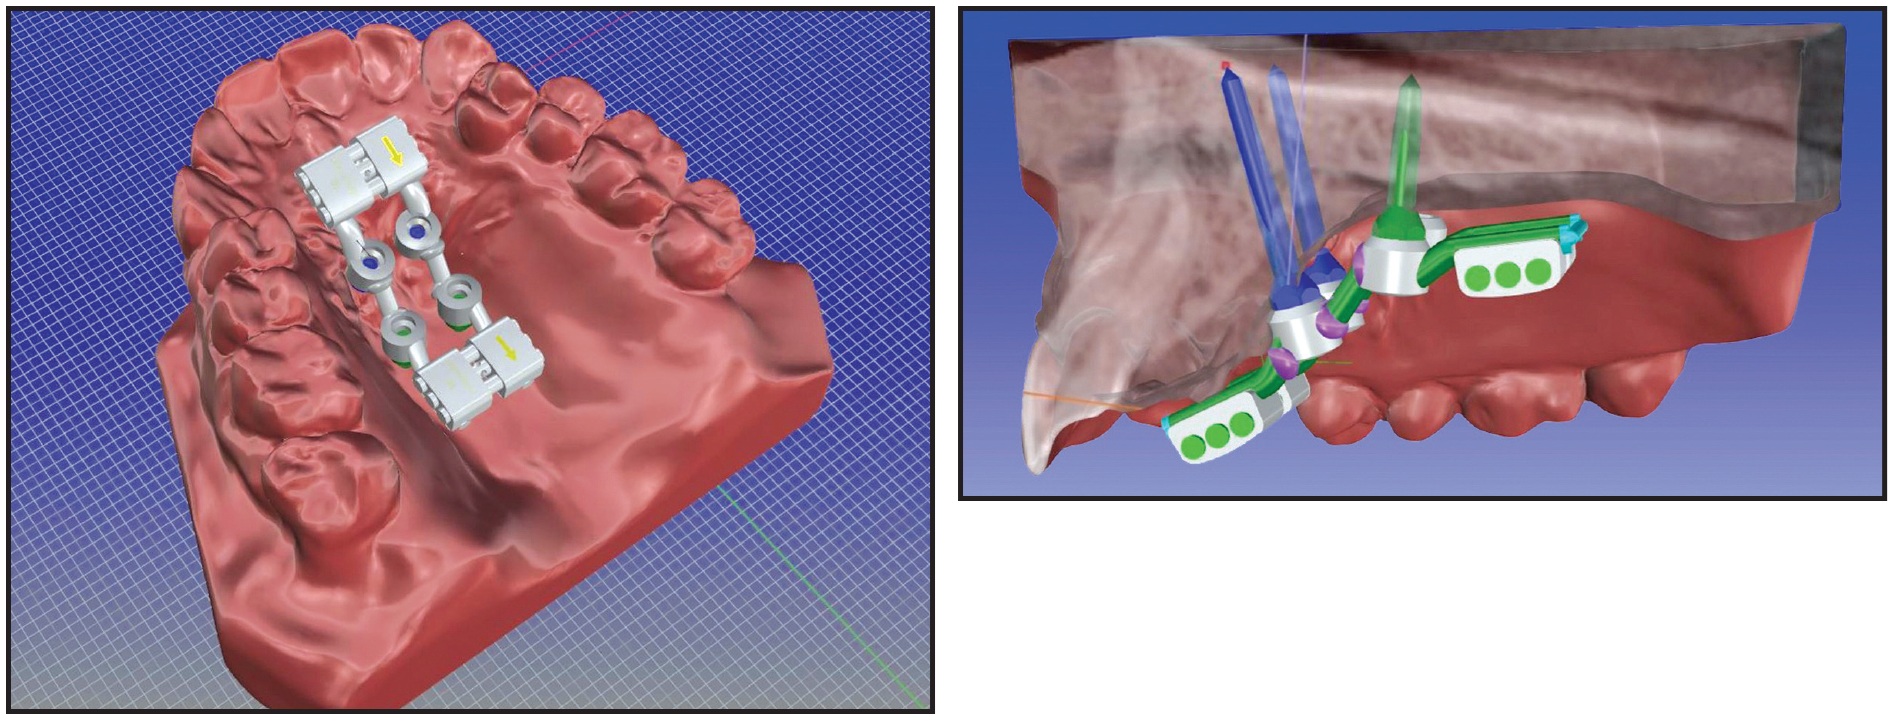

Because both the upper and lower arches had been leveled and aligned, the front teeth were correctly inclined, and the Class III molar and canine relationships were symmetrical, a “surgery first” approach was chosen to correct the transverse discrepancy. In consultation with the maxillofacial surgeon, we planned a noninvasive skeletal maxillary expansion with a boneborne RME. Because of the narrow and high palatal vault, a TSE was used with the MAPA System.

The optimal sites for miniscrew insertion were identified on the CBCT scan, considering the thickness and width of the palatal vault (Fig. 12).

Fig. 12 Case 2. Virtual programming of miniscrew insertion using DICOM images.

Four miniscrews (2mm in diameter) were inserted in the palatal vault: two 15mm miniscrews in the front, one 13mm miniscrew in the posterior right side, and one 15mm miniscrew in the posterior left side (Fig. 13). A TSE was placed, and the patient was instructed to perform two activations per day. The palatal expansion was completed after 21 days, when a diastema had developed between the central incisors as a result of opening the midpalatal suture (Fig. 14).

Fig. 13 Case 2. TSE anchored by four miniscrews.